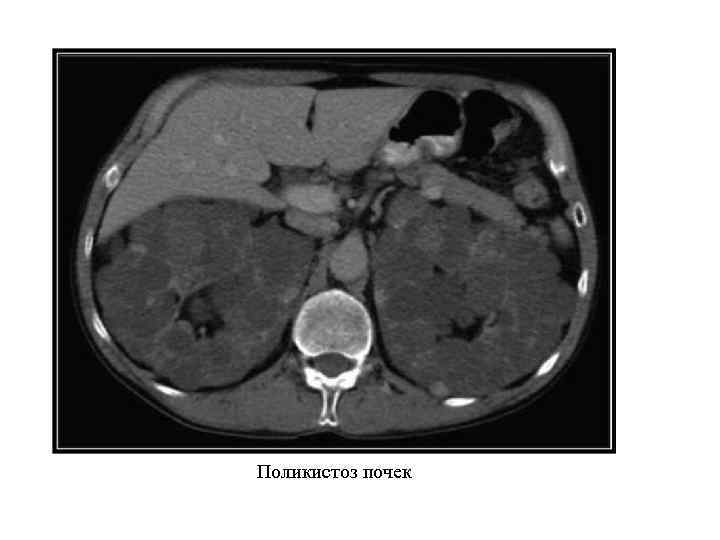

Аномалии структуры почек Дисплазия почки. Мультикистоз почки. Поликистоз почек: поликистоз взрослых; поликистоз детского возраста. Солитарные кисты почек: простая; дермоидная.

Аномалии структуры почек Дисплазия почки. Мультикистоз почки. Поликистоз почек: поликистоз взрослых; поликистоз детского возраста. Солитарные кисты почек: простая; дермоидная.

Поликистоз почек

Поликистоз почек